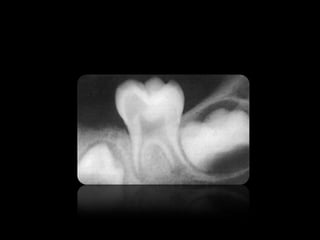

Interpretacion radiográfica

Clase de Interpretación Radiografica presentada por la Dra. Joyce Roca

3.

• Las imagenes

son llamadas radio opacas. • Las imagenes son llamadas radio lúcidas.

CARIES